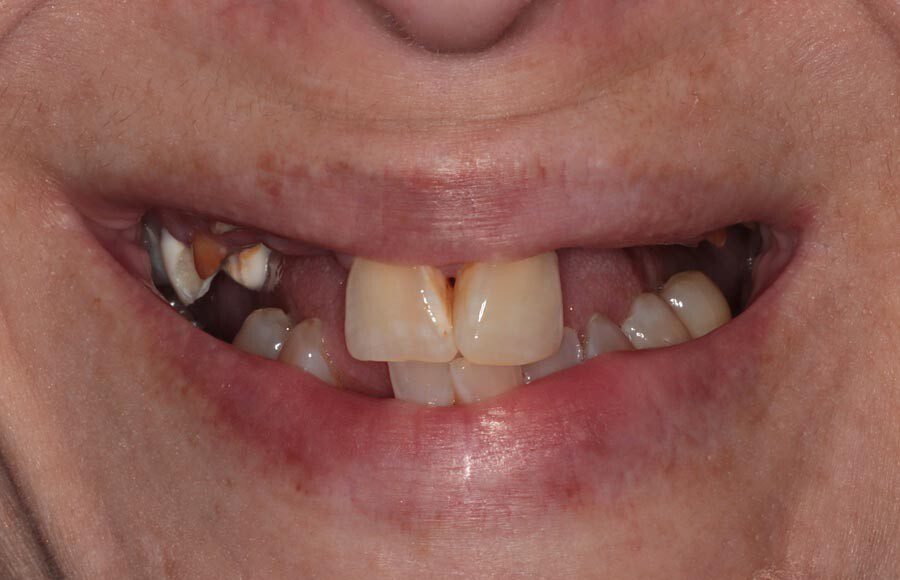

This patient came to our office dissatisfied with her smile. She a history of tooth decay/missing teeth and was looking to improve both her oral health and esthetics.

Her panoramic radiograph shows multiple missing and broken teeth along with tooth decay and areas of infection spreading into the bone.